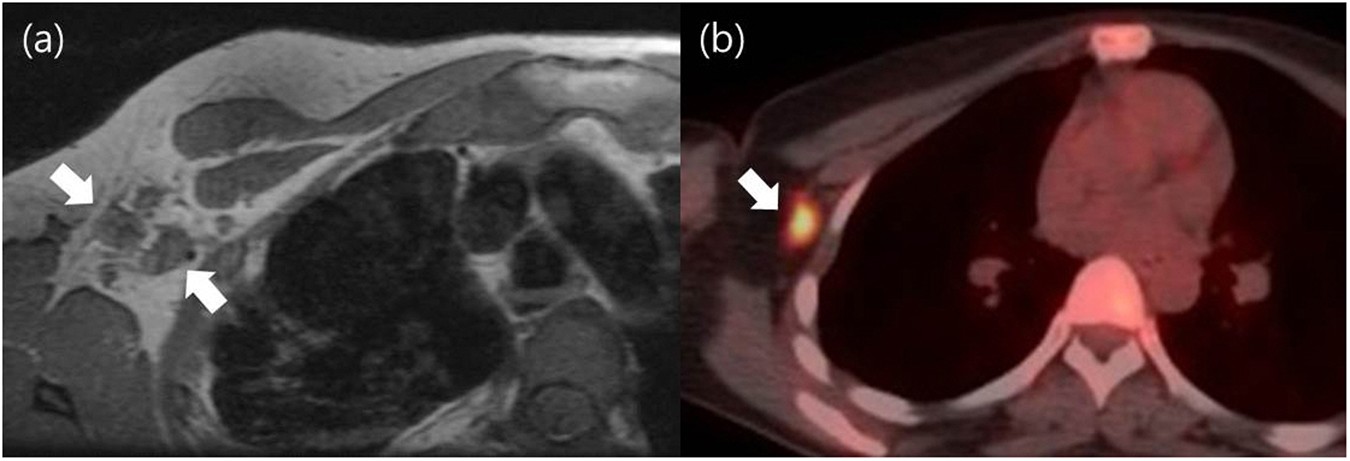

But they can also cause cancer. Ct scans are inaccurate for treatment monitoring after cancer treatment, a ct scan is unable to janice had stage 4 metastatic breast cancer! Ct scans can show a tumor's shape, size, and location. During a breast mri , you lie on your stomach on a padded scanning table. Lung cancer detection, ct scan image, cancer, image processing. Ct scans definition computed tomography (ct) scans are completed with the use of a common ct indications include: By comparing ct scans done over time, doctors can see how a tumor is responding to treatment or find out if the cancer has come back after. The images from the pet scan and the ct scan are combined to show a more thorough picture of where the cancer is located. The risk associated with the thallium heart scans was shocking to me. Stage 3 & 4 community. It takes pictures from different angles. Pet/ct combination scans are used in cancer diagnosis for a variety of tumors where distant metastases are expected (the image above shows a nodule in one of the lungs). You will find a list of common tests, procedures, and scans that doctors use to find the cause of a medical problem.

Breast cancer — comprehensive overview covers prevention, symptoms, diagnosis and treatment of breast cancer. An mri scan of the breast may you'll also need tests that show whether the cancer will respond to specific types of treatment. Research shows that this kind of radiation may damage your dna and lead to breast cancer quiz. They may also do tests to learn if the cancer has spread to a part of the body other than the breast and the lymph nodes under the arm. Pet/ct combination scans are used in cancer diagnosis for a variety of tumors where distant metastases are expected (the image above shows a nodule in one of the lungs).